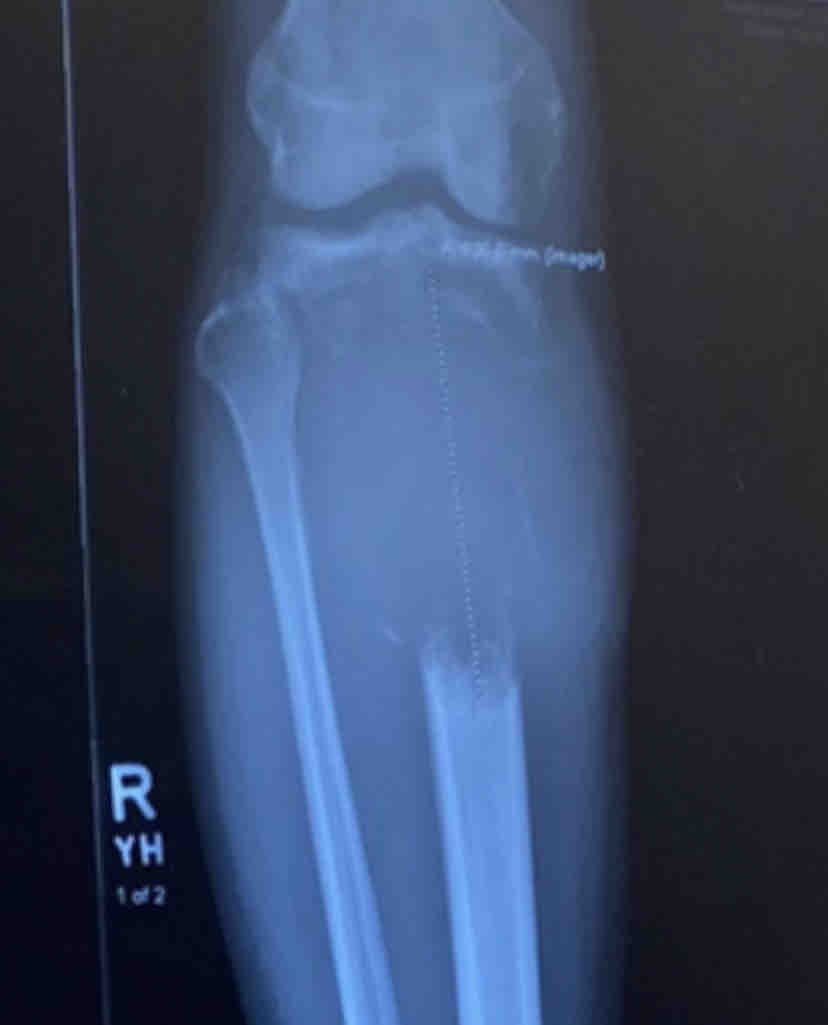

Hello everyone, I am raising funds to help pay for cancer treatment and a prosthetic. Last October I was diagnosed with bone cancer in my right leg after a tumor grew and destroyed a huge portion of bone in my tibia. The cancer had spread to my lungs resulting in a classification of “Stage 4” upon diagnosis. I started chemotherapy that same month and moved back from LA to Florida to be with family in December after a couple sessions. My mom has also been fighting cancer and spent all of last year fighting thru chemo and surgery.

Thankfully After 4 sessions of chemo my tumor shrunk and the cancer in my lungs went away but my tibia bone is past fixing and our only choice is to remove the entire affected portion from my leg. I will need to use a prosthetic for the rest of my life.

I have been on crutches since April 2022 because the tumor started growing around that time and broke my leg which led to the discovery of said tumor. I was unable to begin any serious treatment for 6 months due to issues with medical insurance.